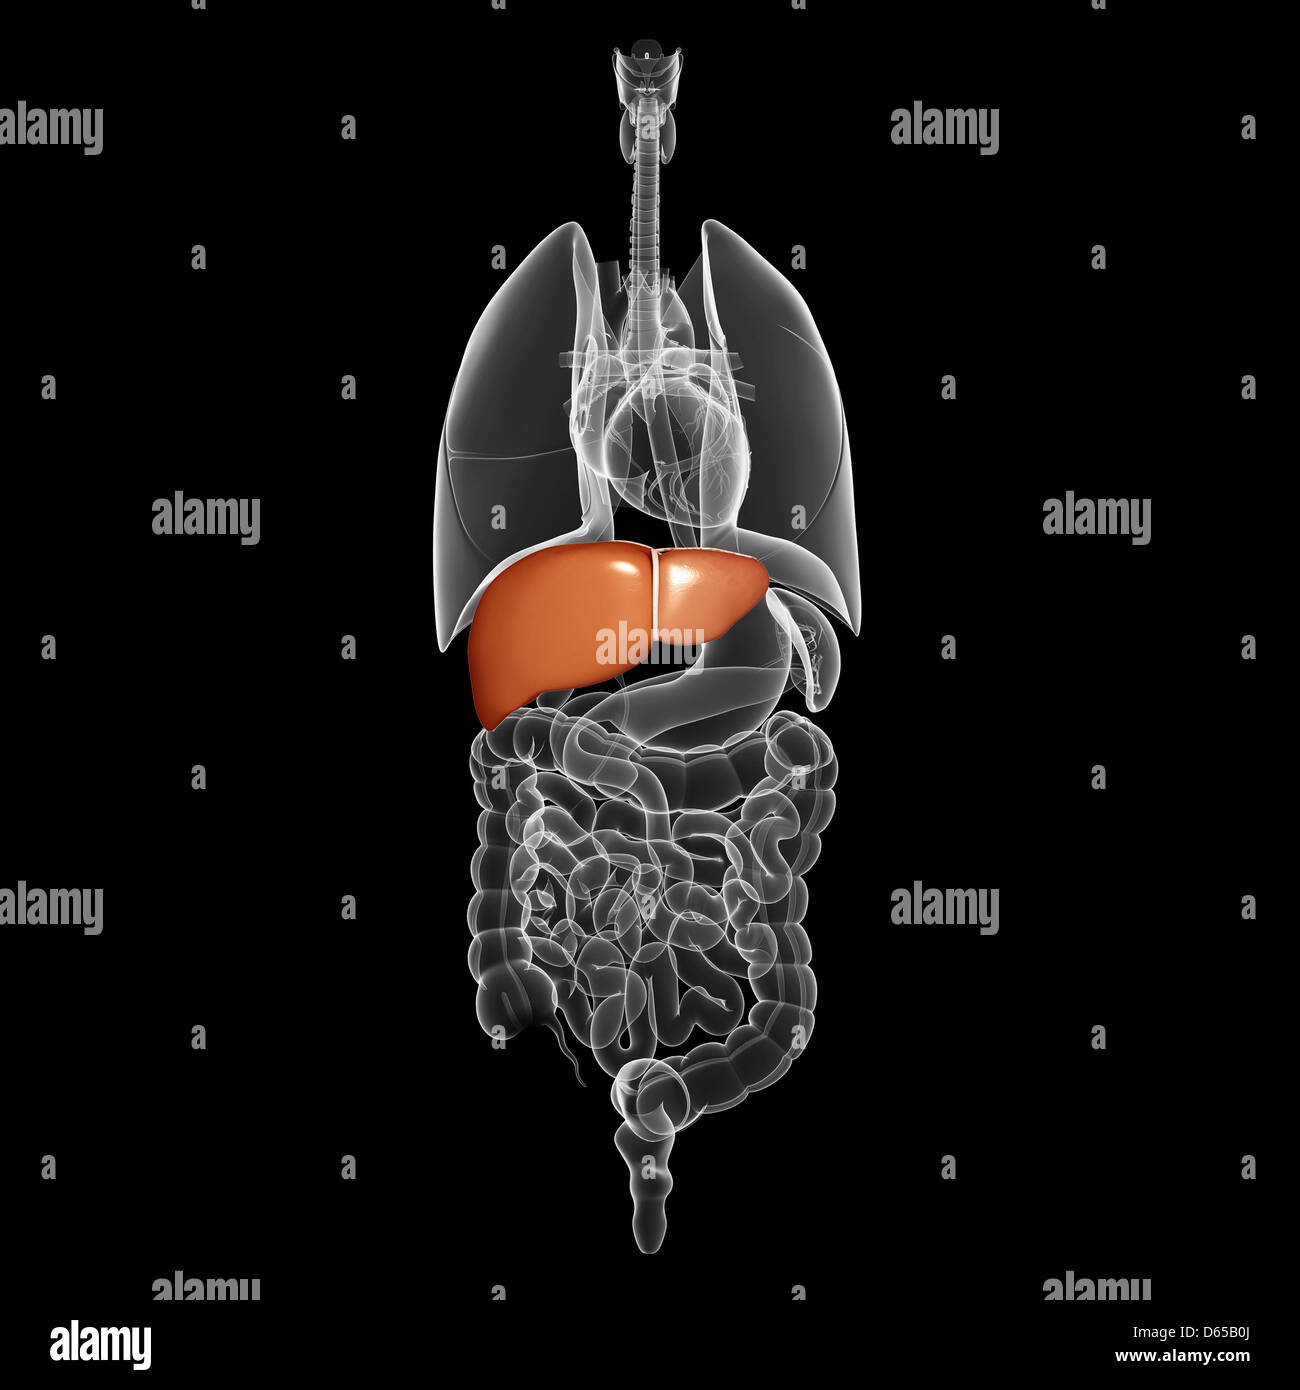

Enlarged liver, X-ray – Stock Image M170/0433 – Science Photo Library

Enlarged liver – Symptoms and causes – Mayo Clinic | Enlarged liver …